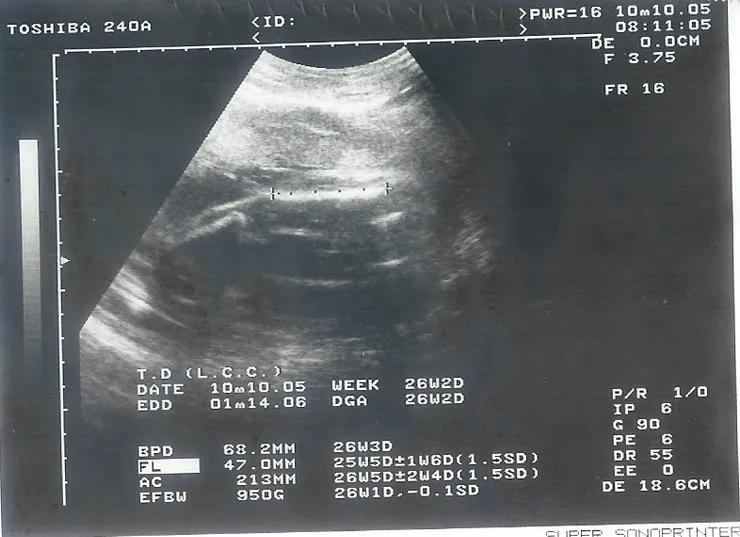

護士給我小咪的超音波照,我問護士這是小朋友的哪裡?她說:「是小朋友的二條腿,要量腿長才能知道小朋友的體重。」我看超音波照上的資料,這次小咪的頭圍是68.2MM,腿長47.0MM,體重950G。